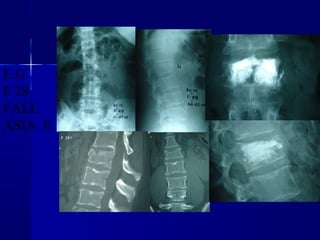

E.G

F 28

FALL

ASIA E

E.G F 28 FALL ASIA E